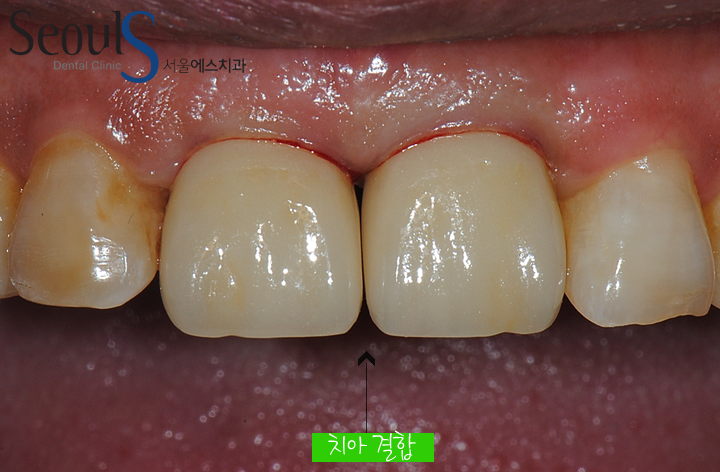

임시 치아를 결합한 모습입니다

임시 치아는 치료 기간 동안 사회 생활하는데 불편함을 덜어드리고

환자분과 보면서 제작 될 치아의 형태와 색, 잇몸 라인에 대해 이야기 하고

여러번의 수정과정을 거칩니다

임시 치아를 보시면 빈 공간을 만들었는데 이는 잇몸이 회복 되는 과정에서 빈 공간을 채우는걸 기대할 수 있습니다